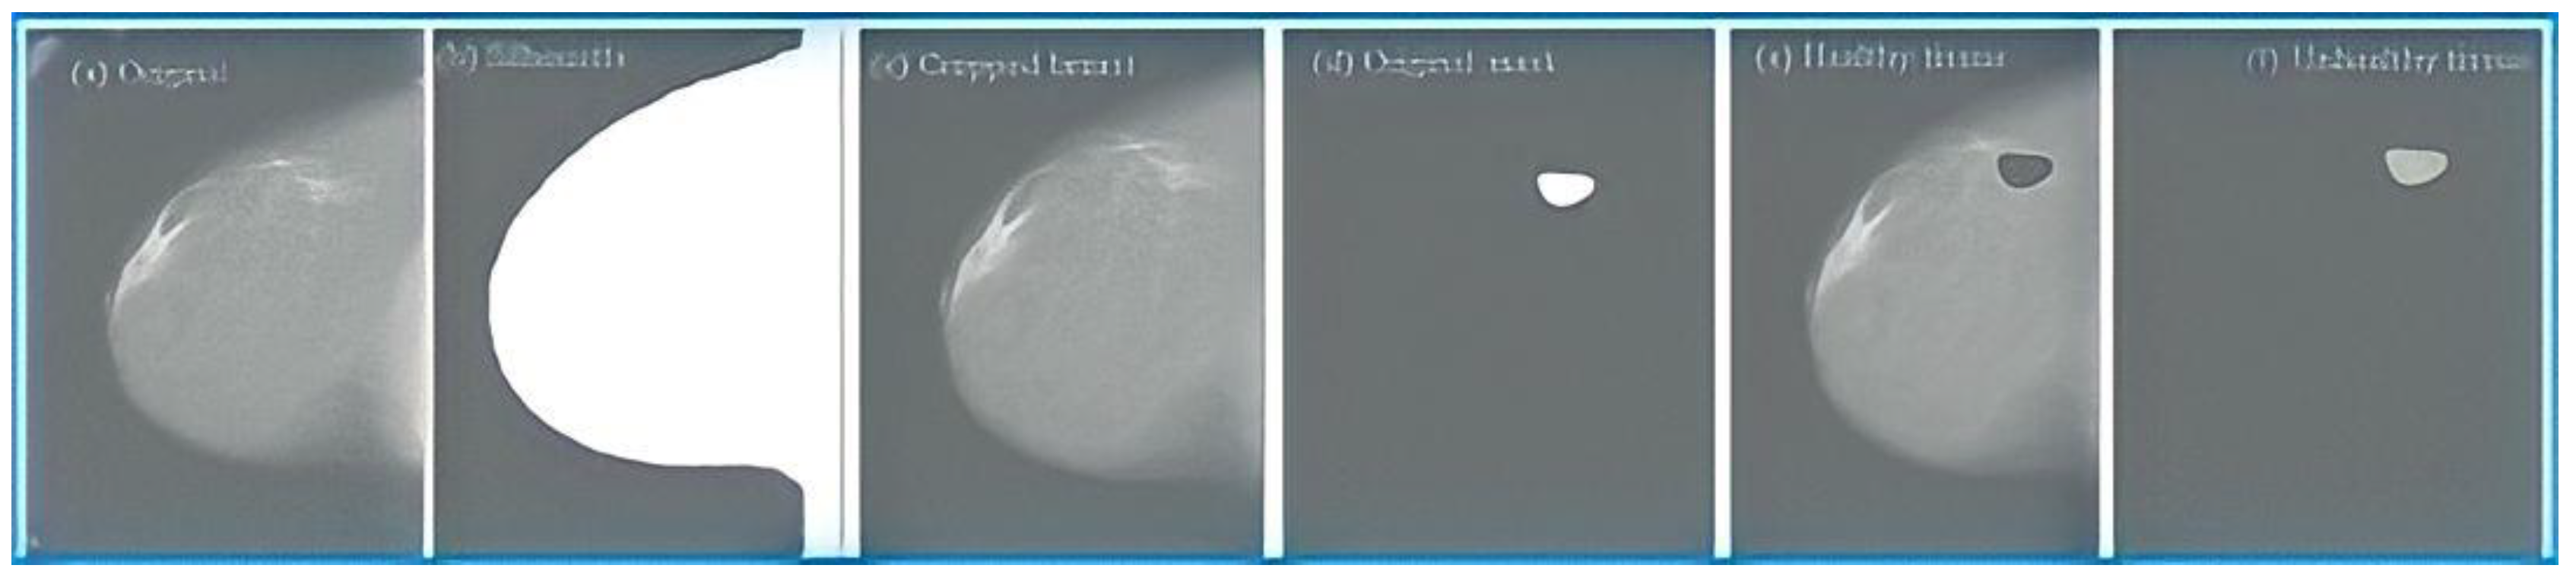

- First, the silhouette of the breast is obtained for each of the mammograms. This silhouette is obtained with equalization of the mammography histogram and a series of morphological operations that allow the contour of the breast to be obtained. Figure 3b shows that the result is a binary image that shows the silhouette of the breast.

- Secondly, the cropped breast is obtained by applying the silhouette obtained in the previous point to the original image, as shown in Figure 1. In the resulting image, the cropped breast will have the silhouette’s edges, but the breast tissue will remain unchanged. In this way, an image is obtained that contains only information about the breast, eliminating the label and other elements that could be in the background. Figure 3c corresponds to an image obtained in this phase.

- After this, the enhanced images containing some pathology have a mask created by radiologists applied to them, which indicates the location of the anomaly (Figure 3d). This mask makes it possible to obtain, on the one hand, the abnormal tissue (Figure 3f), which corresponds to the interior of the mask, and, on the other hand, the healthy tissue, which corresponds to the rest of the tissue (Figure 3e).